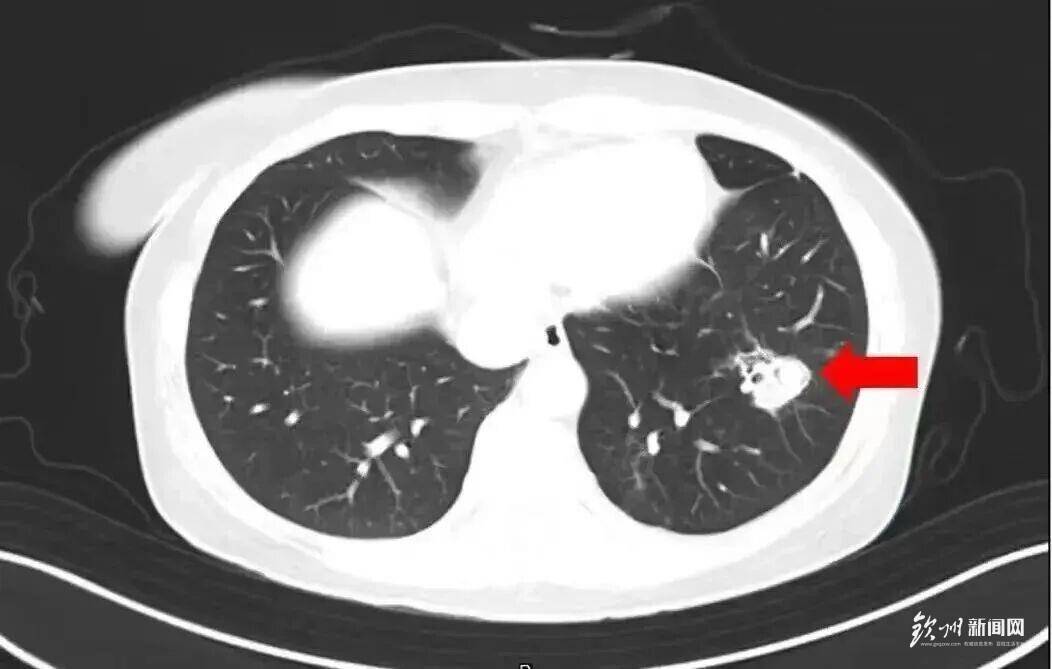

2025年1月,江蘇揚州的張大爺為迎接春節開始大掃除,清掃過程中不慎吸入大量灰塵和霉菌孢子,導致哮喘發作。張大爺隨即服用了常備的哮喘治療藥物,可癥狀反而逐漸加重。經檢查,張大爺的肺部出現感染,確診為肺曲霉病。

北京佑安醫院感染綜合科主任醫師李侗曾介紹,對于免疫力低下的人,吸入了這些真菌,就會發病引起肺部的病變——曲霉肺炎。因為它是通過呼吸道感染的,進入血液后是可以擴散到全身。大腦因為血供最豐富,所以也是真菌最容易侵犯的器官。